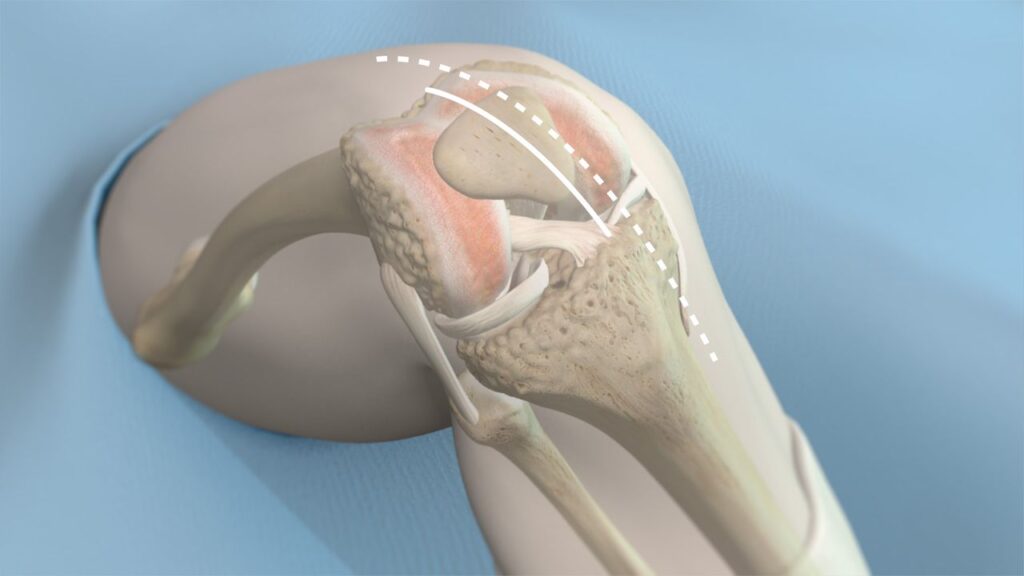

The knee replacement implant components

During a total knee replacement procedure, damaged bone and cartilage are replaced with prosthetic components that mimic the function of your natural joint. These components are carefully selected to restore mobility, stability, and comfort, tailored to your unique anatomy and lifestyle needs.

Knowing the basic structure and function of a knee implant can help you better understand what’s involved in your surgery and what contributes to the success of the outcome.

The femoral component is made of metal (usually a cobalt-chromium or titanium alloy) and is shaped to match the contours of the end of your thigh bone (femur). It curves around the front of the knee and fits into a groove that allows your kneecap (patella) to glide smoothly as the knee moves. This component bears much of the load during walking, squatting, or bending and must be precisely aligned to allow for smooth flexion and extension of the knee.

The tibial component consists of two parts:

Tibial baseplate: A metal platform fixed to the top of your shin bone (tibia) using either bone cement or a press-fit technique.

Tibial insert: A high-grade plastic spacer (made of ultra-high-molecular-weight polyethylene) that sits atop the baseplate.

This plastic insert functions like your knee’s natural cartilage. It cushions the joint, absorbs shock, and allows the femoral component to glide smoothly over the tibial surface. Modern inserts are engineered to be wear-resistant and may include antioxidant-enhanced materials such as Vitamin E to improve durability. In some cases, if only the plastic insert wears out over time, it can be replaced without disturbing the metal implants.

Not all knee replacements require resurfacing of the patella (kneecap), but when it is involved, a small plastic dome is attached to the underside of your kneecap. This enables it to move more smoothly over the femoral component during knee bending and straightening.